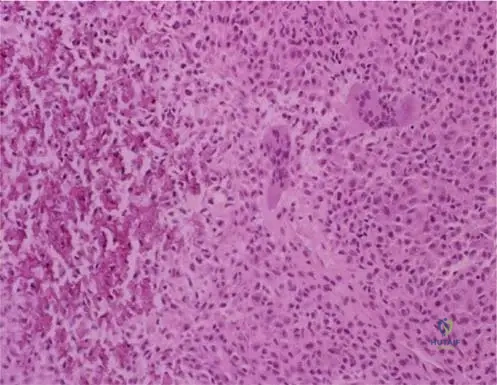

Correct Answer: C

Rationale: Both benign lipomas and atypical lipomatous tumors (ALT) are composed primarily of mature adipocytes and can have fibrous septa. The distinguishing histological feature of an ALT is the presence of scattered atypical stromal cells, often with hyperchromatic, enlarged nuclei, typically found within the fibrous septa. Myxoid degeneration and necrosis are not characteristic features of ALTs; necrosis would suggest dedifferentiation or a higher-grade sarcoma. The main distractor, presence of mature adipocytes, is incorrect because both benign lipomas and ALTs are composed of mature adipocytes; it is the *atypical* features within these cells or stromal cells that differentiate ALTs.

Rationale: The defining histological feature that differentiates an atypical lipomatous tumor (ALT) / well-differentiated liposarcoma (WDLPS) from a benign lipoma is the presence of nuclear atypia and hyperchromasia in the adipocytes, often accompanied by scattered atypical stromal cells and prominent, often thickened, fibrous septa. Mature adipocytes (A) and fibrous septa (B) are present in both benign lipomas and ALT. Myxoid change (D) is characteristic of myxoid liposarcoma, a different subtype. Scattered inflammatory cells (E) are non-specific and can be seen in various benign and malignant lesions.